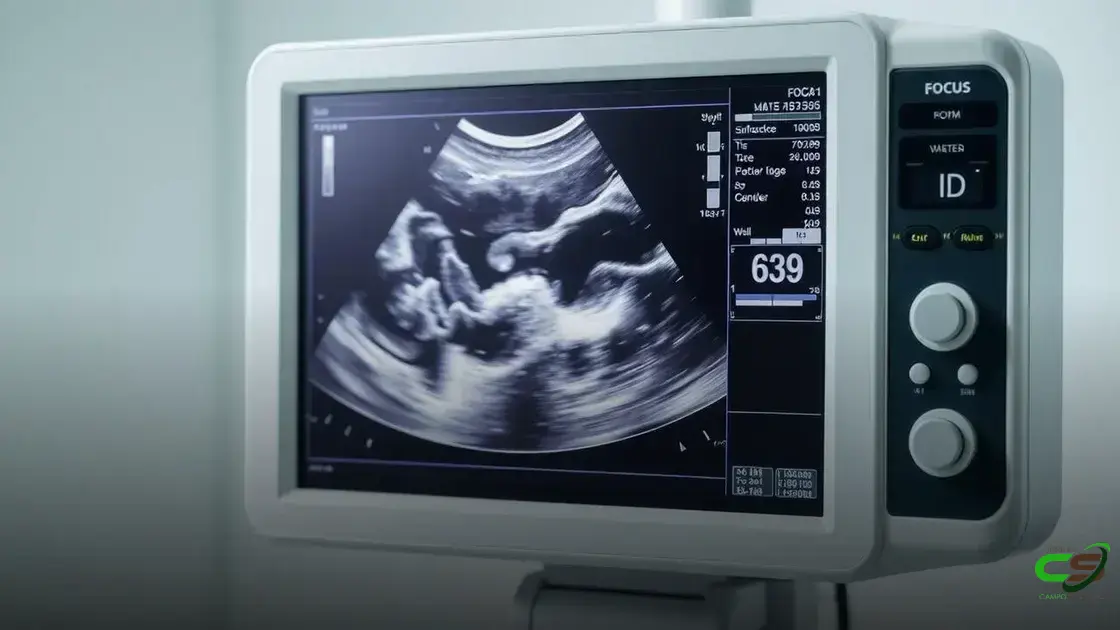

Ultrassonografia de Carcaça Impulsiona Rentabilidade na Pecuária Moderna

Descubra como a ultrassonografia de carcaça está transformando a pecuária brasileira e aumentando os lucros desde a desmama.